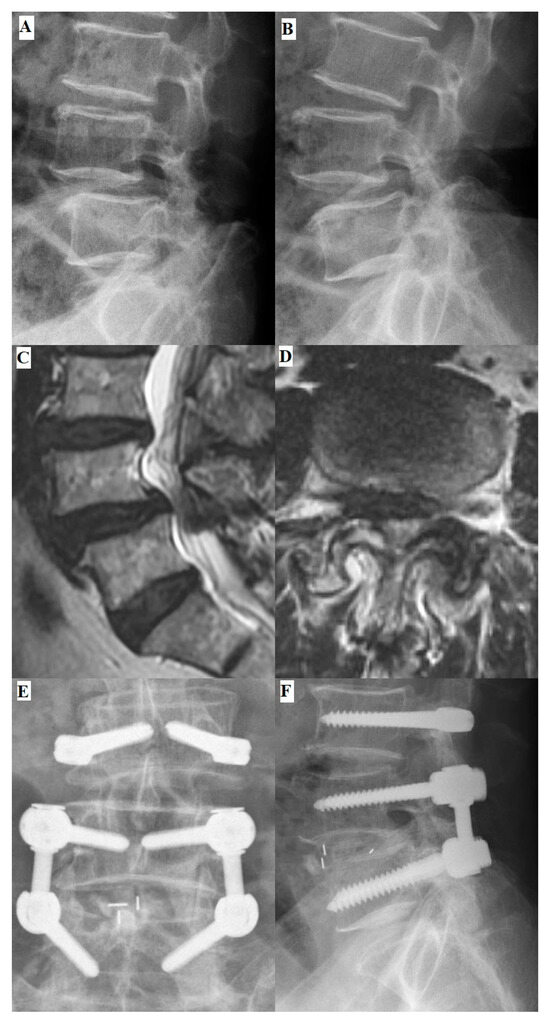

1. Introduction

2. Material and Methods

2.3. Surgical Techniques